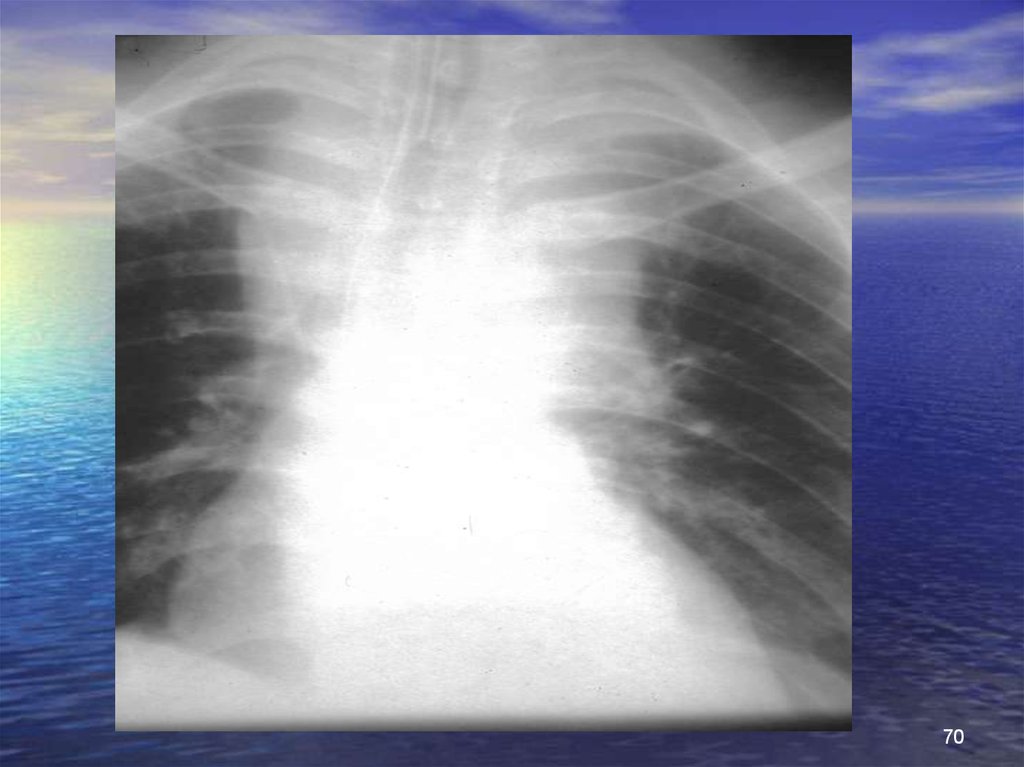

70.

70